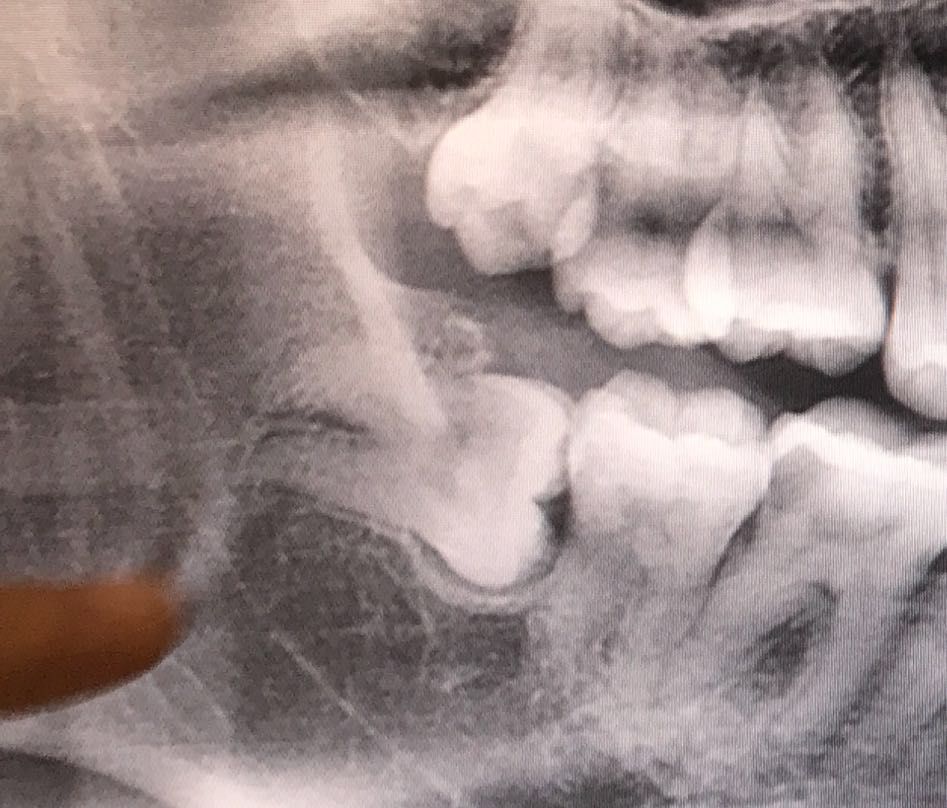

前几天终于鼓起勇气,把右边长得奇形怪状,顶着磨牙,还老塞东西的智齿给拔了。问过深圳这边的公立医院牙科,也问了之前就诊过很多次的私立口腔,都说我这根智齿根骨惊奇,需要费不少功夫,收费怎么也得1000-1500吧。

等拍了更精准的片子,私立口腔的干脆说,花2000,请我们院长出马给你搞定,保管活好!上面那颗简单点,就600元吧。

牙科门诊的主任拿着大小不同的钻头和牙铤(对,现在不用锤子砸了!改用长得很像螺丝起子的东西撬)在我嘴里一阵捣鼓。30分钟过去了,下方横着长的智齿碎成了10片渣渣,之后又用了5分钟,把上智齿拽了下来。

如果是长得很正的智齿拔除,确实不用费什么功夫,几分钟就卸下来。但是横着长的智齿,需要用十八般兵器把牙冠大卸八块,再把牙根取出来,还要避免伤害到牙神经和牙槽骨,自然就费很多功夫,价钱也就不一样了。

智齿姿势越销魂,拔除价格越戳心。我的智齿就是第三种姿势。